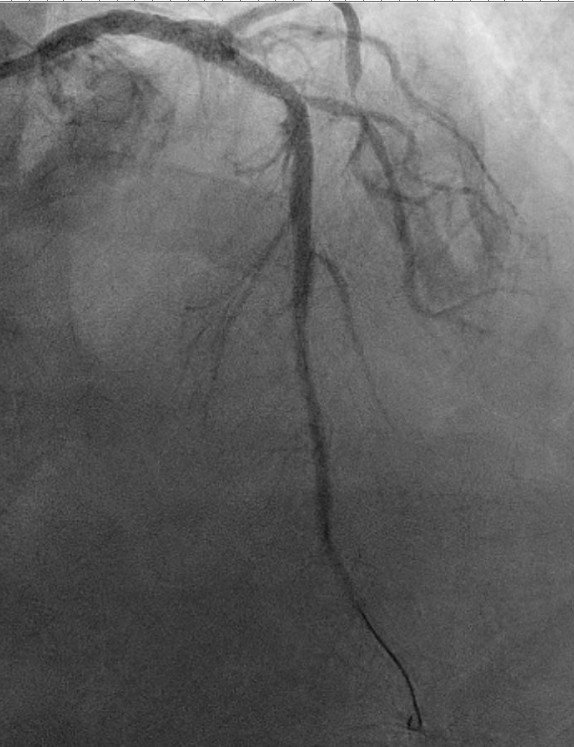

Angiogram showed culprit total occlusion of the proximal LAD.

Despite PCI, cardiogenic shock progressed on the cath lab table. Impella was used, and the patient was intubated for progressive respiratory failure.